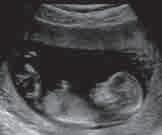

Ултразвучна дијагностика

би се снимила унутрашњост

Ове фреквенције су превисоке да би их људско ухо могло чути. Део ултразвучних таласа, као и свих таласа, при наиласку

тразвучној дијагностици се

рефлексије или еха (одјека) звучних таласа. Ултразвучно снимање је посебно добро у откривању цисти, које су џепови течности у јетри, жлездама